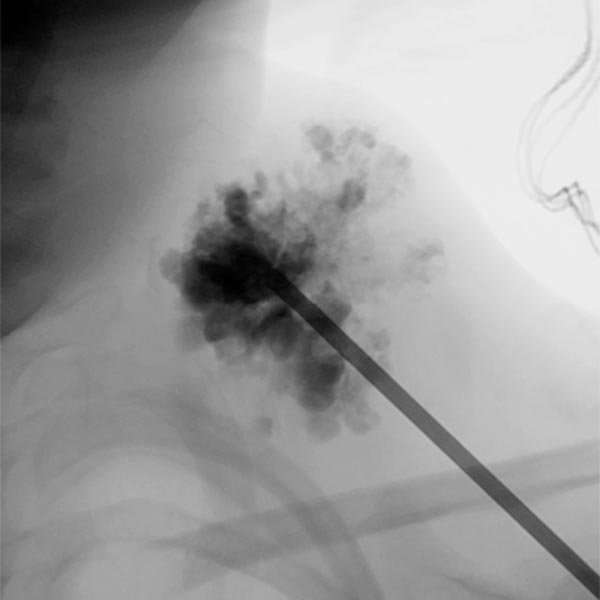

In der Durchleuchtungskontrolle (seitliche Ebene) nach Injektion von 8 ml Polidocanol-Schaum (3 %, 1 : 4 in Luft aufgeschäumt) ist die gesamte venöse Malformation mit dem nicht kontrastierenden Schaum ausgefüllt. Das vorher enthaltene Kontrastmittel ist praktisch vollständig durch den Sklerosierungsschaum verdrängt. Damit besteht eine sehr gute Chance, dass die Läsion sehr weitgehend durch den Eingriff verschlossen wird.